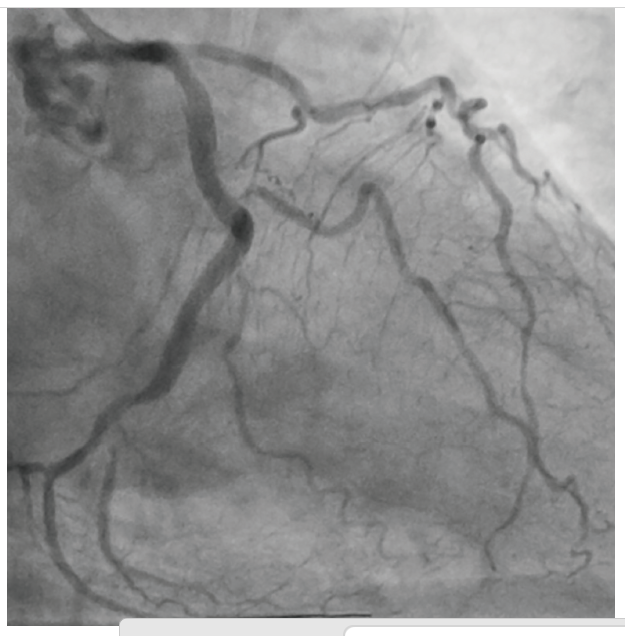

An 81-year-old male with hypertension, diabetes, and hyperlipidemia was referred for evaluation of an abnormal stress test. He originally complained of shortness of breath with exertion. A pharmacologic stress test was performed at an outside facility and showed inferior wall ischemia with a normal ejection fraction. He underwent coronary angiography via a right radial approach that revealed a heavily calcified, eccentric lesion in the large, codominant circumflex artery with TIMI-3 flow (Figure 1). Due to a small ulnar artery, the decision was made to access the right femoral artery in preparation for complex intervention. Utilizing a 6 French Judkins Left 4 guide catheter, the left system was engaged. The lesion was wired with a Runthrough® Izanai™ wire (Terumo Interventional Systems) and pretreated with balloon angioplasty using a 2.0 mm x 15 mm Takeru™ RX balloon (Terumo Interventional Systems) (Figure 2). A 2.5 mm x 15 mm Takeru™ RX noncompliant (NC) balloon was then advanced to perform further pre-dilation balloon angioplasty (Figure 3).